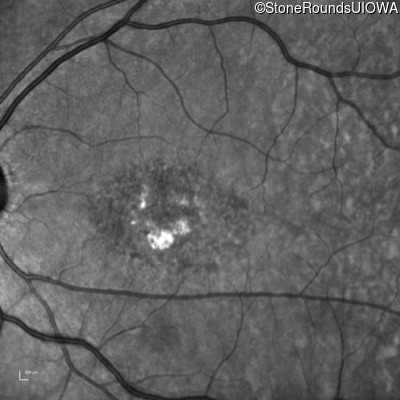

Infrared Fundus Photograph - Left - 20/50 -1

Exemplar